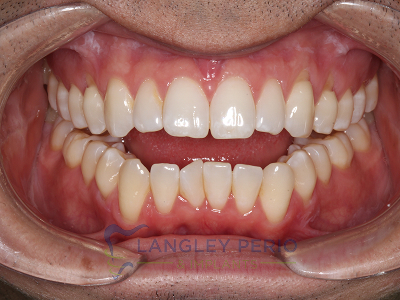

Case 3

Alloderm tissue grafting performed to improve root coverage and esthetics. This technique does not require tissue to be taken from the patient’s palate.